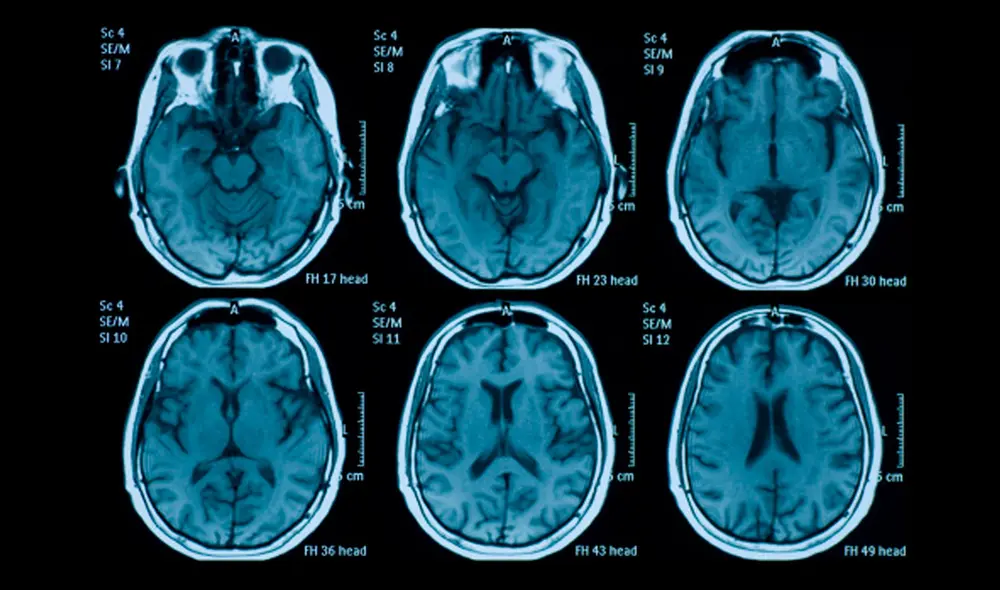

A cada voluntario se le realizó una resonancia magnética tras cada noche. Esta información permitió a los científicos comparar cómo se veían los cerebros antes y después de la privación del sueño, y luego de un descanso completo.

Para determinar las edades aparentes de los cerebros de los participantes, los investigadores utilizaron un algoritmo de aprendizaje automático llamado brainageR, el cual fue entrenado con resonancias de más de 3.000 personas, de modo que puede predecir cómo se ve el órgano cerebral sano a una edad determinada.

En el nuevo estudio, los científicos aplicaron el algoritmo para predecir las edades antes y después de las pruebas de sueño.